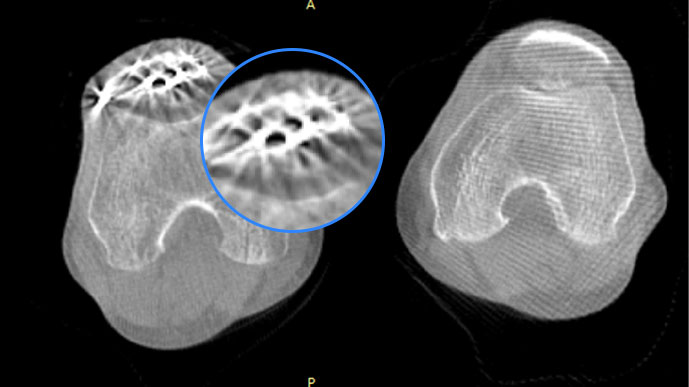

关闭金属伪影校正

开启金属伪影校正